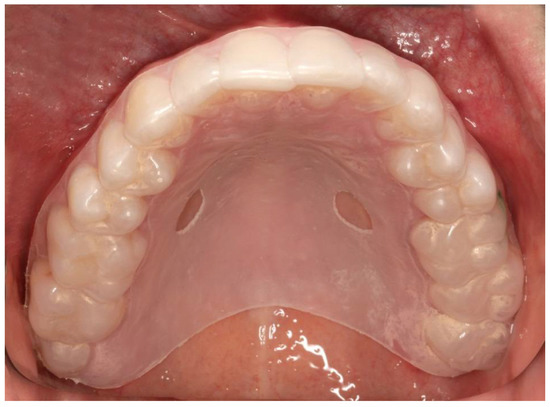

2. Materials and Methods